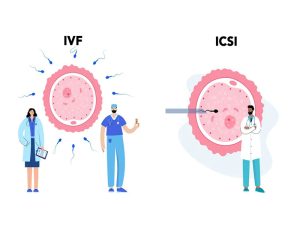

تفاوت میکرواینجکشن با آی وی اف در چیست؟

تفاوت میکرواینجکشن با آی وی اف در درمان ناباروی